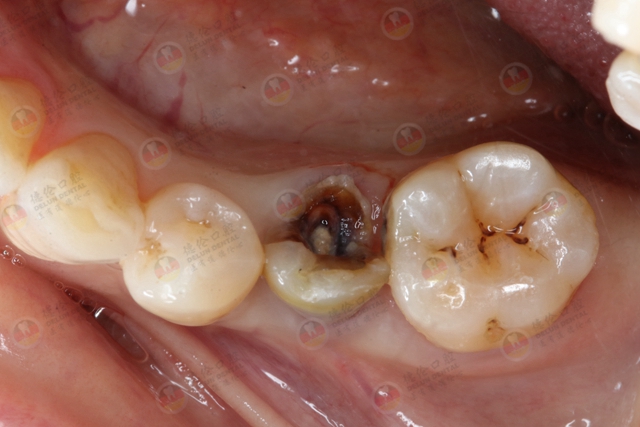

#01、根尖周炎

根尖周炎大多是牙髓疾病的继发病,主要由根管内的感染通过根尖孔作用于根尖周组织引发。

而随着感染不断深入和扩大,牙根周围的牙槽骨也会被慢慢破坏,发生吸收,此时,感染产生的脓液便会在牙龈上形成脓包,脓包时大时小,有脓性分泌物。

导致根尖周炎的疾病主要有龋齿和牙齿外伤。

龋齿严重,累及牙髓,发生了牙髓炎,长期得不到治疗就容易发生根尖周炎,进而出现牙龈脓包。